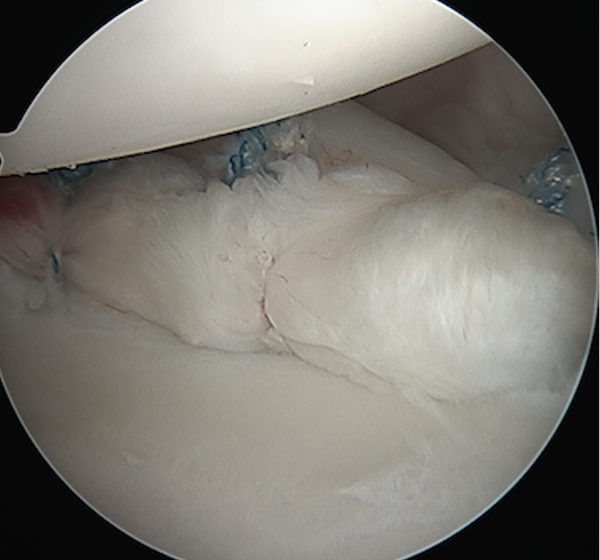

Posterior capsular plication

- option 1: Suture plicate capsule to labrum

- option 2: Anchors in glenoid and use to plicate capsule to labrum

Posterior capsular plication with suture anchors